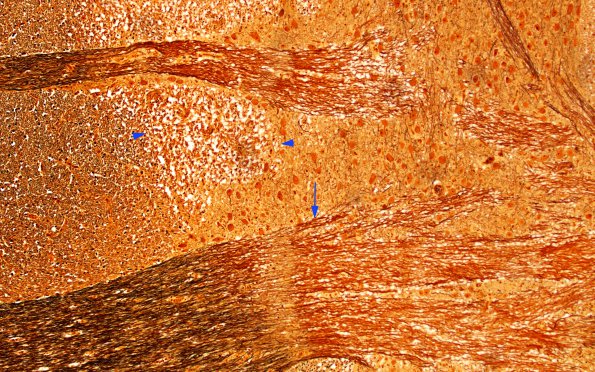

Washington University Experience | MYELIN (IMMUNE-MEDIATED) | MS - Brainstem & Cerebellum | 3B6 MS (Case 3) N11 Biels 10X copy

Higher magnification images (10X) of the ventral pontine plaque stained for axons (Bielschowsky). The plaque contains an area of descending (arrowheads) and transverse (arrow) fibers as well as neurons, all of which appear well maintained.